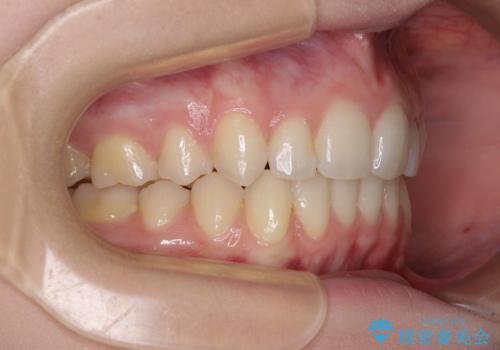

八重歯を短期間で改善 ワイヤー装置による抜歯矯正

- 著しい八重歯を気にして来院された患者様です。

片側の八重歯であり上顎の正中がずれていたため、上顎左右第一小臼歯2本を抜歯して排列することとしました。

下顎の骨格的なズレが大きかったため、上下歯列のバランスが取れるか心配でしたが、上下ともに左右対称に近い歯列で治療を終えることができました。